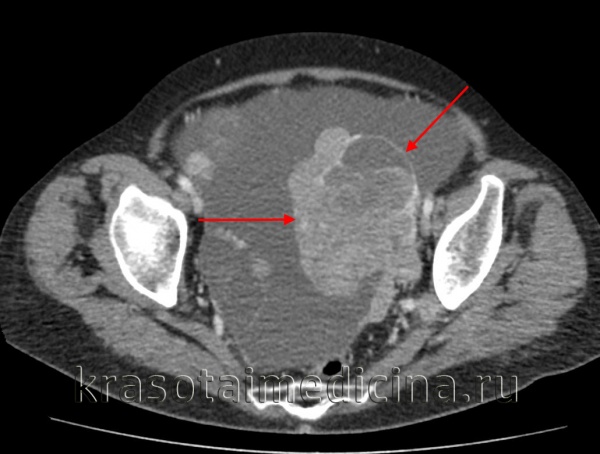

(Слева) Трансвагинальная ультрасонография: отмечается, что дермоид может иметь нехарактерную картину визуализации на ультрасонографии при условии, что мягкотканный компонент будет преобладать над жировым. Данный дермоид гетерогенно эхогенный и заполняет замкнутое пространство кзади от матки.

(Справа) КТ с контрастированием того же образования, аксиальный срез: определяется относительно небольшое количество жира с преимущественно мягкотканным компонентом, что формирует специфичную картину визуализации на ультрасонографии.